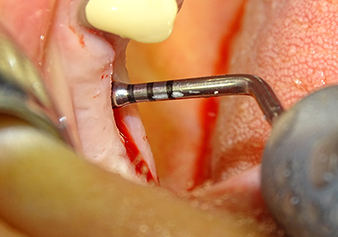

The Schneiderian membrane is carefully detached with the Z25P instrument (phase 1)

Fig.3: Following marking of the implant position and initial expansion of the bed, the Schneiderian membrane is carefully detached with the Z25P instrument (phase 1).

Following atraumatic preparation of the mucoperiosteal flap, the implant position was marked with the I1 instrument and the site prepared – until initial resistance was felt. Piezosurgical instruments were used in an up and down movement without any pressure being exerted. The piezoelectric vibration produced the desired and efficient cavitation.

The I2A instrument (diameter 2.0 mm) was then used to perforate the sinus floor intermittently and on the smallest scale possible. This special piezosurgical method ensures that the Schneiderian membrane is not damaged. When the Z25P was used, the membrane was already lifted slightly by the coolant supplied via the instrument tip (Fig. 3). The coolant quantity was just 50% in order to avoid high pressure in the implant bed.